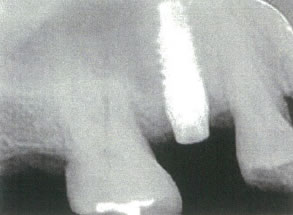

インプラント治療には、健康な骨が必要です。

インプラントの周囲には健康な骨が必要です。